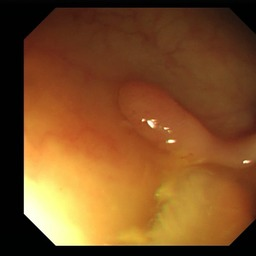

Medical image segmentation is a primary task in many applications, and the accuracy of the segmentation is a necessity. Recently, many deep learning networks derived from U-Net have been extensively used and have achieved notable results. To further improve and refine the performance of U-Net, parallel decoders along with mask prediction decoder have been carried out and have shown significant improvement with additional advantages. In our work, we utilize the advantages of using a combination of contour and distance map as regularizers. In turn, we propose a novel architecture Psi-Net with a single encoder and three parallel decoders, one decoder to learn the mask and other two to learn the auxiliary tasks of contour detection and distance map estimation. The learning of these auxiliary tasks helps in capturing the shape and boundary. We also propose a new joint loss function for the proposed architecture. The loss function consists of a weighted combination of Negative likelihood and Mean Square Error loss. We have used two publicly available datasets: 1) Origa dataset for the task of optic cup and disc segmentation and 2) Endovis segment dataset for the task of polyp segmentation to evaluate our model. We have conducted extensive experiments using our network to show our model gives better results in terms of segmentation, boundary and shape metrics.